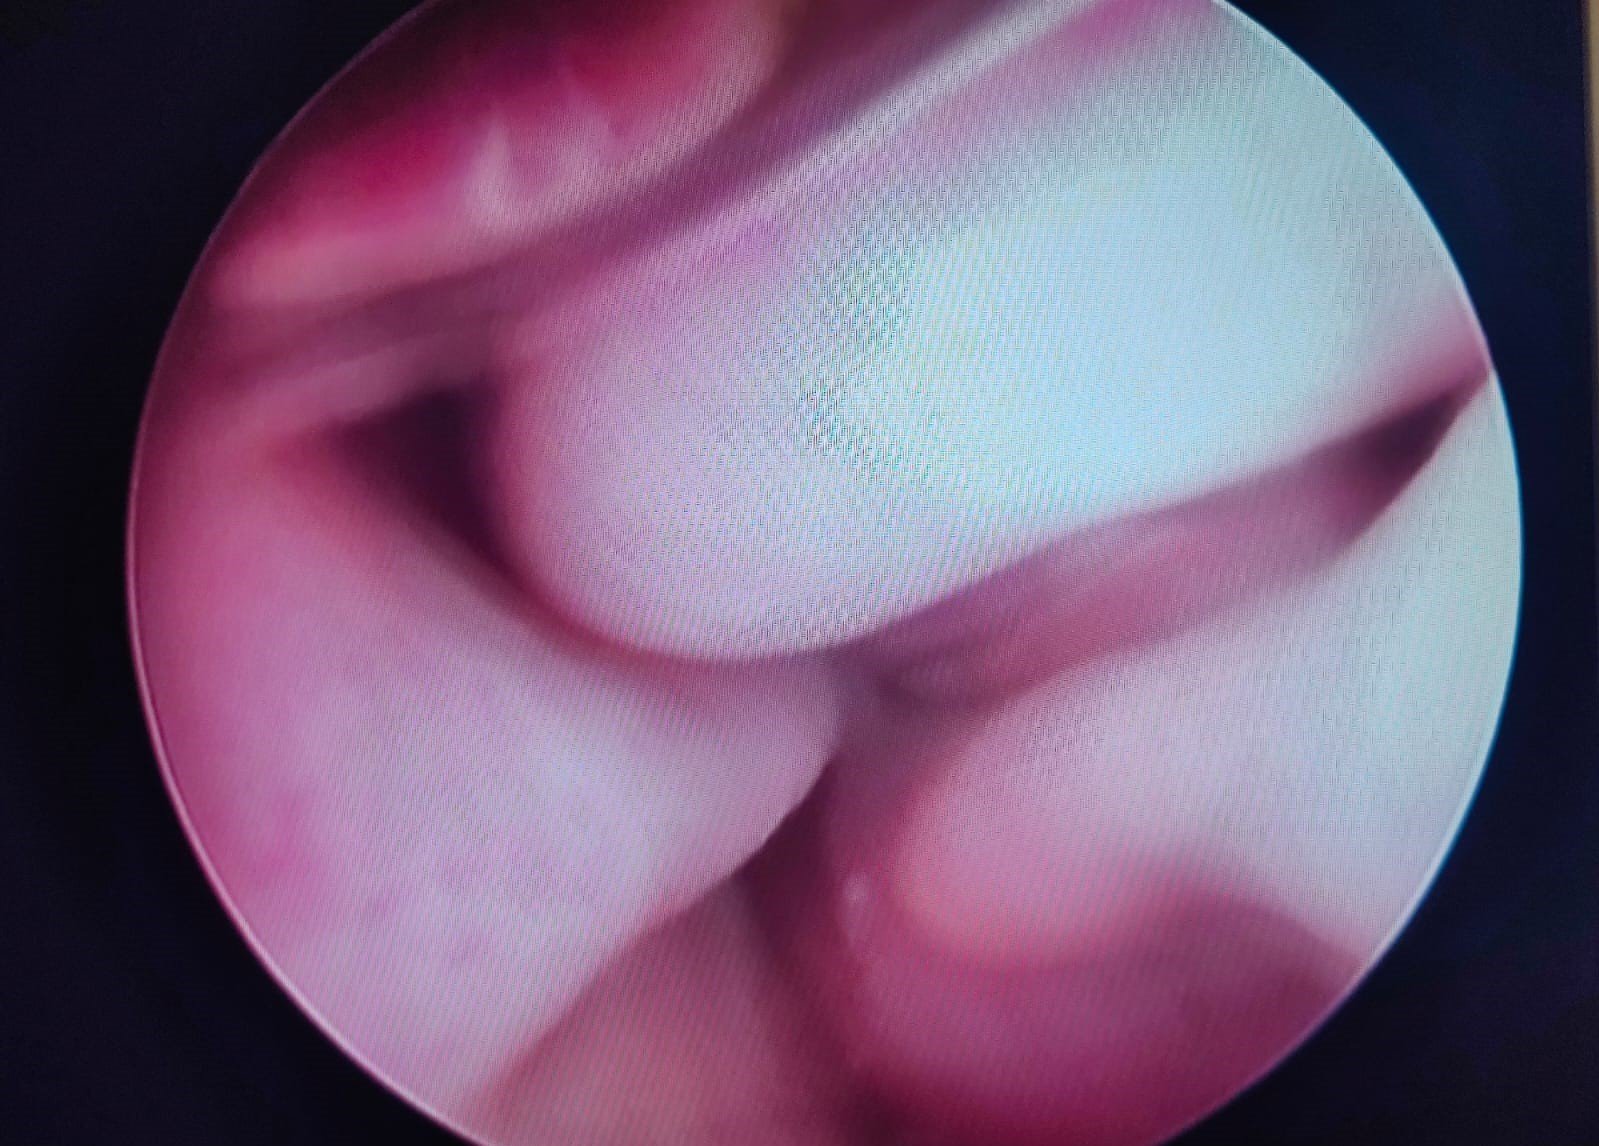

La video otoscopia è un ausilio diagnostico fondamentale nelle indagini del canale auricolare in corso di otiti e corpi estranei. Tramite questo strumento si rende possibile l’asportazione di materiale patologico all’interno dell’orecchio e l’esame completo del canale auricolare e del timpano. La tecnica viene eseguita in anestesia generale per ottenere il miglior risultato senza dolore per il paziente

Timpano e orecchio in condizioni fisiologiche